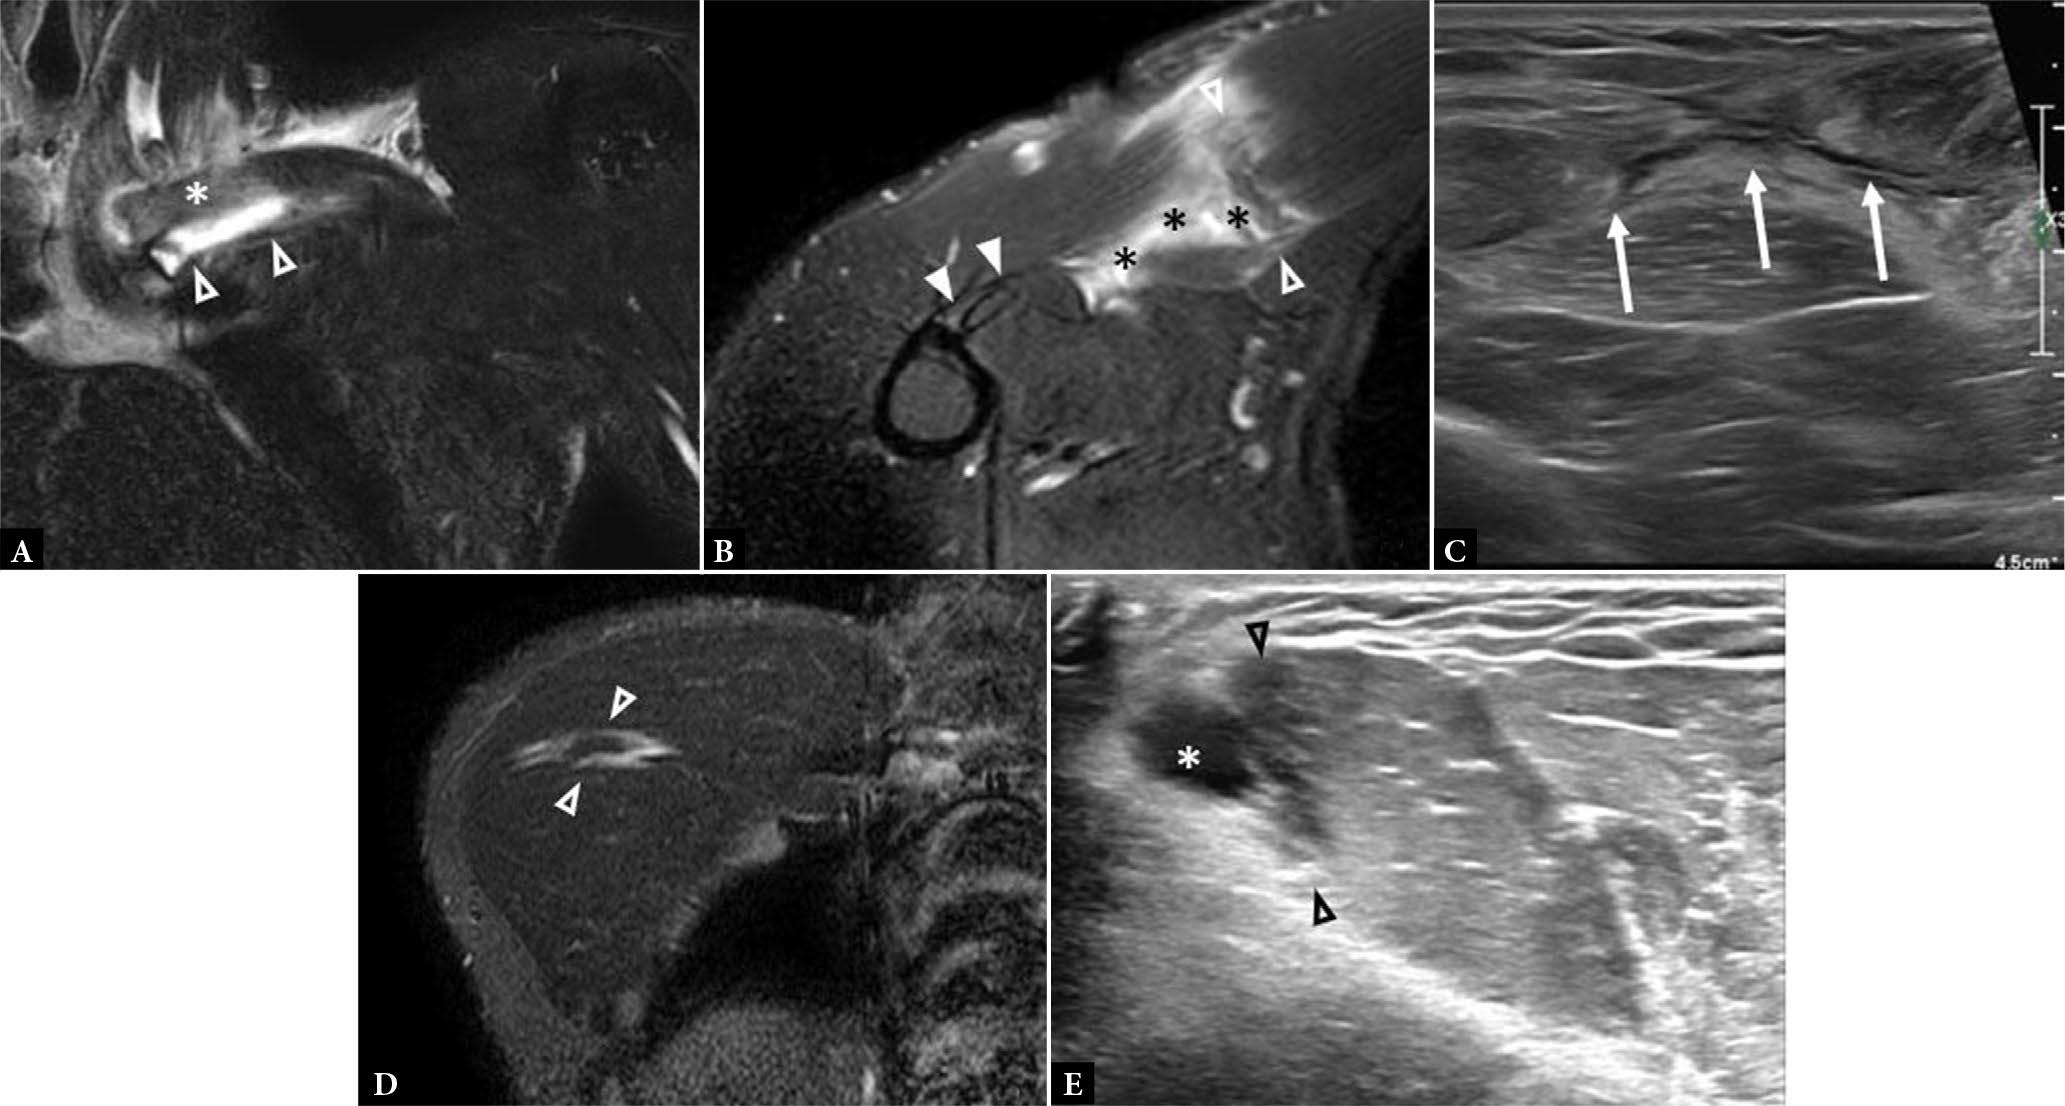

Fig. 7.

A. Coronal fluid-sensitive MR image shows a PM tear at the clavicular head origin with edema (arrowheads) interposed between the clavicle (asterisk) and the muscle. B. Axial fluid-sensitive MR image shows a PM tear at the myotendinous junction (between empty arrowheads) with edema, fiber disorganization, and surrounding poorly organized hematoma (asterisks). Note intact tendon insertion onto the humerus (solid arrowheads). C. Short axis gray scale ultrasound image shows feathery anechoic fluid (arrows) tracking along the expected course of the pectoralis muscle fibers in the setting of intramuscular PM tear (not shown). D. Coronal fluid-sensitive MR image shows an intramuscular PM tear with edema and discontinuous fibers (arrowheads). E. Long axis gray scale ultrasound image shows an intramuscular PM tear with intramuscular edema at the site of tear (arrowheads) and more focal anechoic abnormality that represents a small intramuscular hematoma (asterisk)

Coronal (A) and axial (B) fluid-sensitive MR images show diffuse, feathery signal hyperintensity in the PM muscle (open arrowheads) without fiber disorganization or laxity, consistent with PM strain. C. Long axis gray scale ultrasound image in another patient demonstrates increased echogenicity and poorer fiber conspicuity in a patient with strain of the clavicular head of the PM (asterisk). Note the normal architecture of the adjacent deltoid muscle (arrowhead). There is no frank fiber disruption or disorganization in these images to suggest tear

Fig. 15.

A. Axial fluid-sensitive MR image shows hyperintensity in the PM muscle. B–D. Post contrast axial T1 MR image with fat saturation (B) shows a region of peripheral enhancement (asterisk) in the medial fibers of the PM with corresponding high diffusion weighted imaging (C) and low apparent diffusion coefficient (D) values, in keeping with intramuscular abscess. Note the similarity in appearance of Figures 15A and 14B, underscoring the importance of clinical history